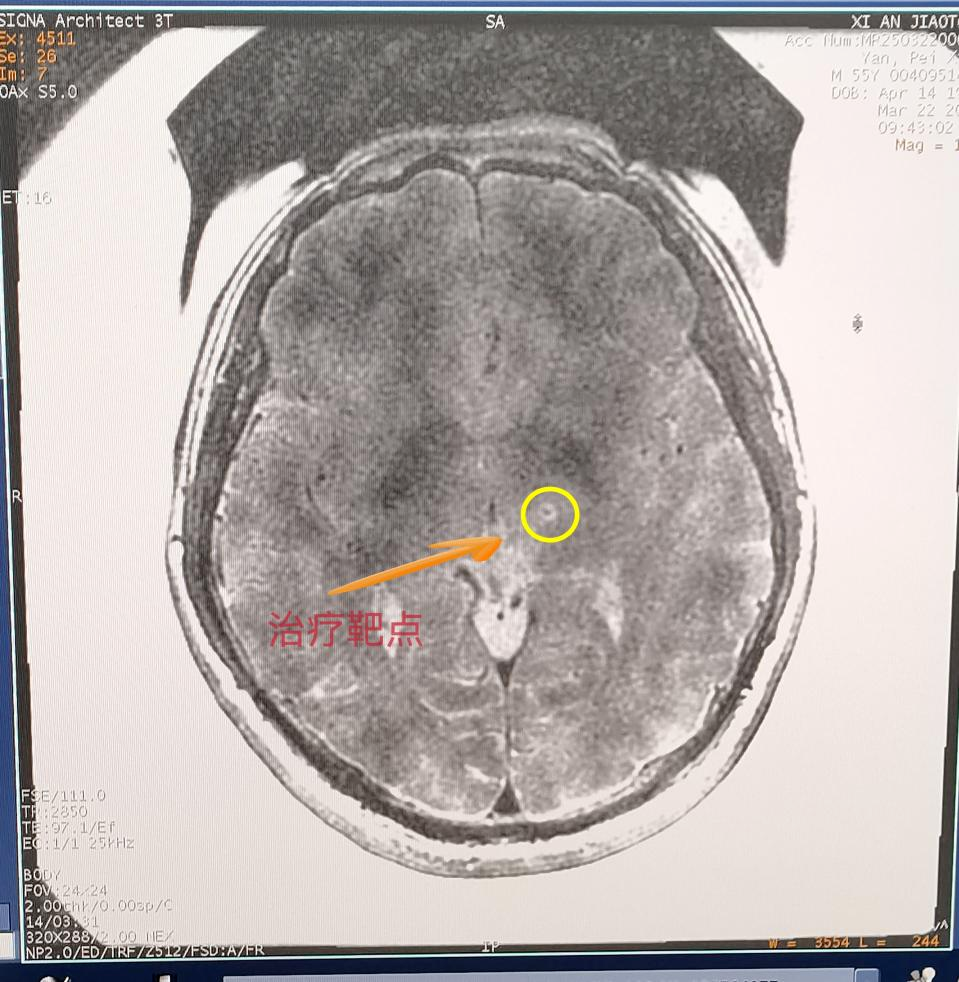

交大一附院神經(jīng)外科陳偉教授從病例出發(fā),詳細(xì)向大家講述了磁波刀技術(shù)原理,分享應(yīng)用案例并展示治療效果。

這項(xiàng)革命性技術(shù)融合了磁共振導(dǎo)航與聚焦超聲技術(shù),通過(guò)高精度磁共振鎖定腦內(nèi)異常神經(jīng)靶點(diǎn),運(yùn)用聚焦超聲波束穿透顱骨實(shí)施靶點(diǎn)高溫消融,從而阻斷震顫信號(hào)傳導(dǎo)。整個(gè)過(guò)程無(wú)需開(kāi)顱,真正創(chuàng)造出“隔山打?!钡尼t(yī)學(xué)奇跡。在治療過(guò)程中,閆先生在清醒狀態(tài)下躺入磁共振室,在醫(yī)生的嚴(yán)密監(jiān)護(hù)下,陳偉醫(yī)生通過(guò)最先進(jìn)的SIGNA Architect 3.0T磁共振系統(tǒng)鎖定閆先生腦內(nèi)異常神經(jīng)靶點(diǎn),運(yùn)用1024束精準(zhǔn)聚焦的超聲波穿過(guò)顱骨,精準(zhǔn)抵達(dá)大腦異常靶點(diǎn)。僅需15秒便讓震顫完全消失。這種無(wú)創(chuàng)、無(wú)痛的方式,不僅安全高效,還讓閆先生當(dāng)場(chǎng)感受到顯著改善。